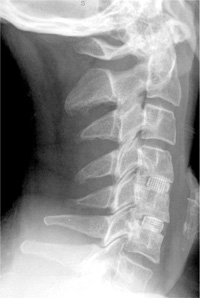

Fig. 2 Photograph showing a polyetheretherketone (PEEK) cervical

cage (Kage) containing 60:40 hydroxyapatite : tricalcium phosphate

(HA:TCP) biphasic calcium phosphate (KG Bone).